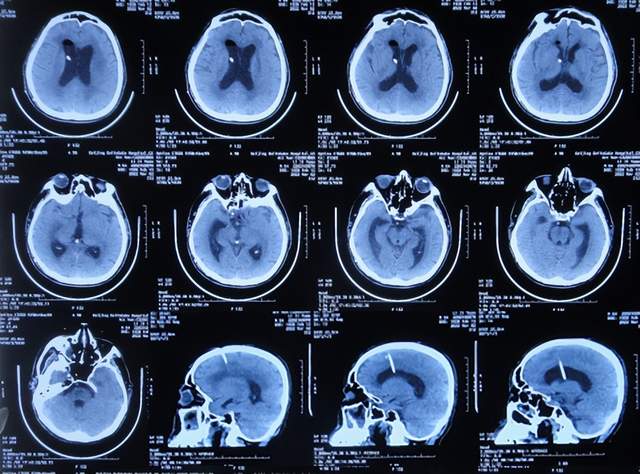

患者于2021年9月2日突发昏迷,急送至当地的山东省滨州市惠民县某医院,查头颅CT示脑出血破入脑室(图-1),急诊行双侧脑室外引流术;脑出血后血压偏低,给予输注入人血白蛋白。

图-1:2021年9月2日头颅CT

术后次日即2021年9月3日,患者意识转清醒,能简单言语,肢体可以遵嘱抬起;查头颅CT示双侧脑室引流术后,脑室积血(图-2)。

图-2:2021年9月3日头颅CT

双侧脑室外引流术后3天即2021年9月5日,查头颅CT示脑室内积血减少(图-3)。

图-3:2021年9月5日头颅CT

双侧脑室外引流术后6天即2021年9月8日,再次查头颅CT示仍有少量积血(图-4);给予常规拔除了双侧脑室外引流管,同时进行了腰大池引流术。

图-4:2021年9月8日头颅CT

腰大池引流术后4天即2021年9月12日,查头颅CT示脑室内积血基本消失(图-5)。

图-5:2021年9月12日头颅CT

拔除腰大池引流管后3天即2021年9月23日,查头颅CT示(图-6)后继续给予保守治疗。

图-6:2021年9月23日头颅CT

腰大池引流管拔除后13天即2021年10月3日,患者恢复至可以搀扶下行走约20米,能简单言语,查头颅CT较2021年9月23日认为没有明显变化(图-7)。

图-7:2021年10月3日头颅CT

但继续保留治疗20余天的时间内,患者逐渐出现意识变差,走路变差,至2021年11月3日(腰大池引流管拔除后31天),病情变重致不能走路,不能言语,查头颅CT(图-8)后考虑脑积水,给予腰椎穿刺治疗。

图-8:2021年11月3日头颅CT

但腰椎穿刺治疗7天病情无明显改善,于2021年11月10日(住院治疗2月余)出院回家休养,出院时头颅CT示仍有脑积水(图-9);出院时:意识差,不能走路,不能言语。

图-9:2021年11月10日头颅CT

出院1个半月后,因患者病情无改善,家属想做脑室腹腔分流术,于2021年12月22日前往上级的山东省滨州市某三甲医院就诊,查头颅CT示脑积水(图-10);但腰椎穿刺检查示颅内压低;胸部CT有肺部脓肿(片子丢失),暂时给予抗感染治疗。

图-10:2021年12月22日头颅CT

给予抗感染治疗个月后即2022年1月17日,肺部脓肿明显变小(片子丢失),查头颅CT仍脑积水(图-11),未给予脑室腹腔分流术,建议暂时回家休养,但患者意识仍不好,不能走路,不能说话,体型变消瘦。

图-11:2022年1月17日头颅CT

入院时查头颅CT示脑积水(图-13);肺部CT示肺部感染(图-14)。

图-13:2022年2月16日头颅CT

入院次日,给予脑室外引流术,查头颅CT示脑室外引流术后状态(图-15)。

图-15:2022年2月17日头颅CT

2022年3月1日(入院治疗13天),病情进一步改为:意识便完全正常,大小便变正常,扶着能坐起,言语交流变基本正常(图-17);头颅CT示脑室变小(图-18)。

图-18:2022年3月2日头颅CT

2022年4月7日(入院治疗50天),查头颅CT示脑室引流术后状态,未见异常(图-22)。

图-22:2022年4月7日头颅CT

2022年4月27日(入院治疗70天)家属要求出院回家休养。出院时:携带脑室腹壁外引流管;精神变得挺好,能自己站立但自己走路不稳,体重较入院时明显增加,入院时消瘦病态的体型已基本恢复正常状态(图-23);出院时头颅CT示脑室引流状态(图-24)。

图-24:出院时头颅CT

出院后4个月即2022年8月30日,为了做脑积水分流术,再次来到李小勇脑脊液科,入院时:精神状态良好,能自己走路了稍不稳(图-25);头颅CT示脑室引流术术后状态(图-26)。

图-26:2022年8月30日头颅CT

完善各项检查后于2022年9月15日,进行了脑室腹腔分流术(图-27)。

图-27:2022年9月15日头颅CT